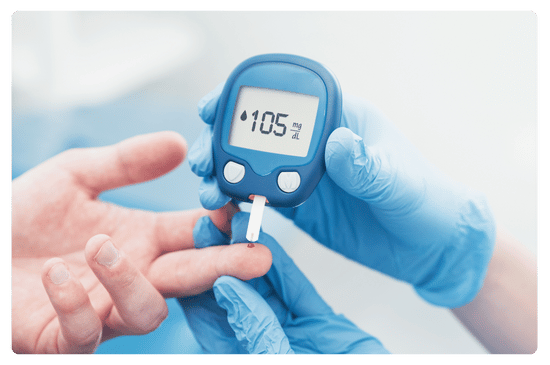

The Comprehensive Guide to Diabetes Reversal: Understanding, Strategies, and Success Stories